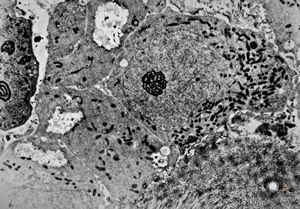

M,3y. | globoid leukodystrophy of Krabbe - n.suralis